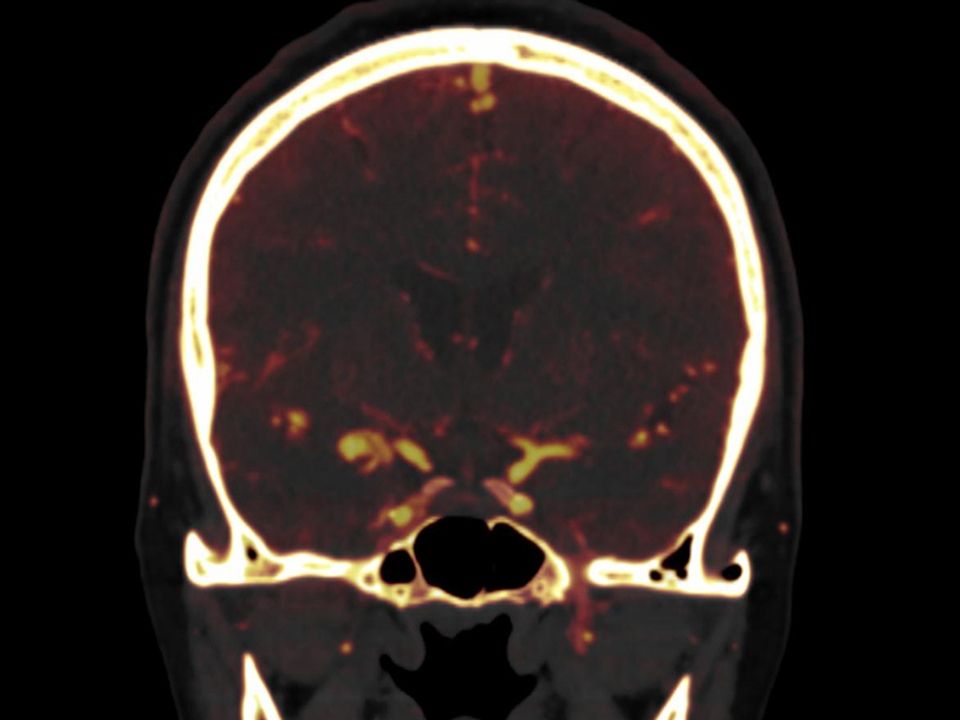

CT DE Brain Hemorrhage

Differentiate hemorrhage from iodine-uptaking bleedings and lesions.